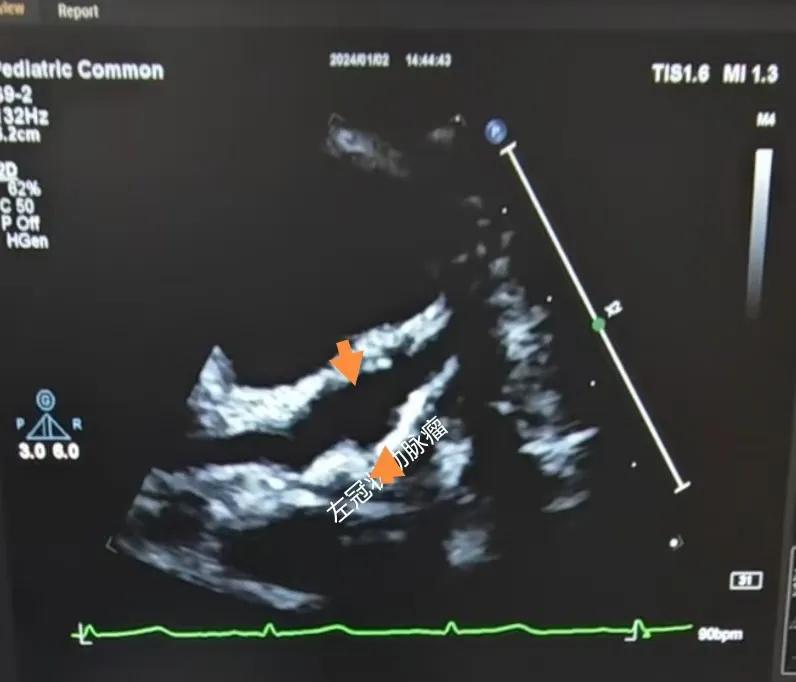

(川崎病患兒:增寬的右側(cè)冠狀動脈)

(川崎病患兒:左冠狀動脈瘤)